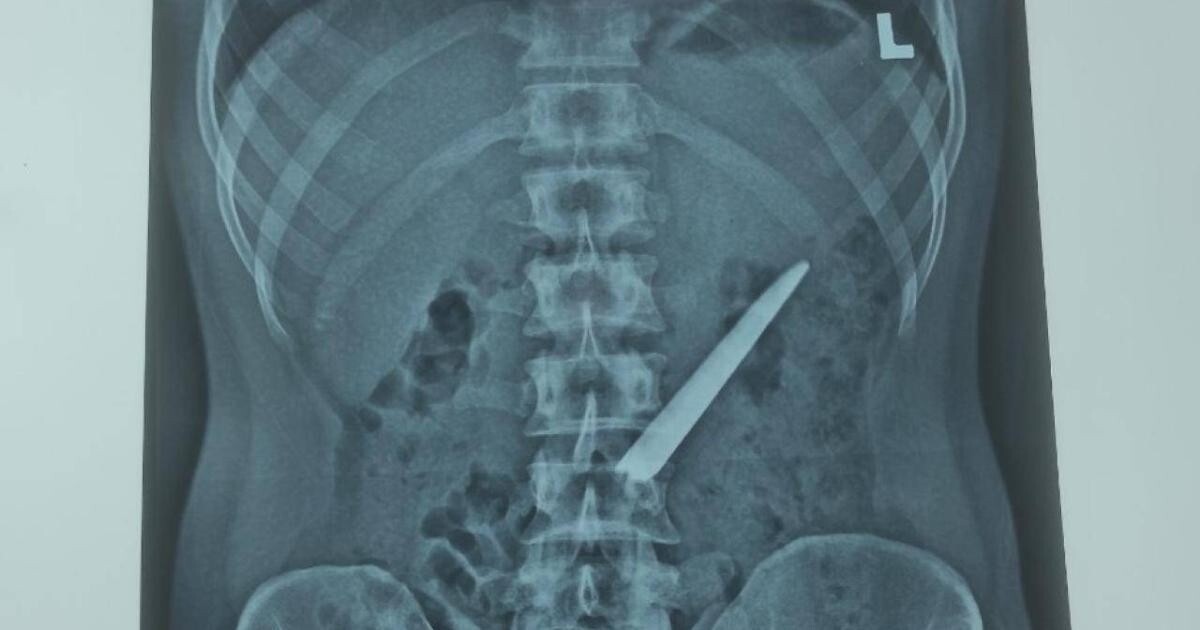

Sau khi thăm khám và nội soi, các bác sĩ phát hiện một vật sắt nhọn dài khoảng 10cm (lưỡi dao Thái Lan không có cán) nằm bên trong bụng đoạn giữa tá tràng.

Ngay sau khi chẩn đoán, các bác sĩ đã tiến hành phẫu thuật hở. Sau gần 1 giờ phẫu thuật, các bác sĩ đã gắp thành công dị vật ra ngoài.